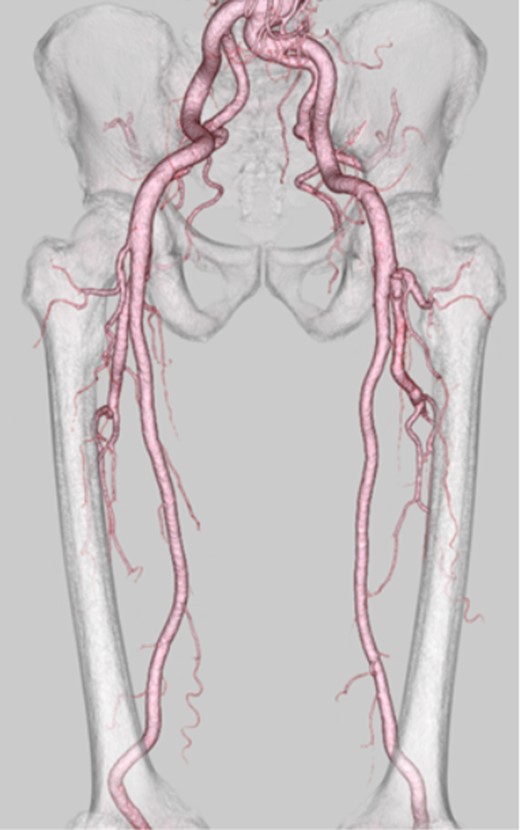

The surgery was performed through a longitudinal groin incision. The sartorius muscle was preserved by splitting it along the muscle fibers. The DFA aneurysm was 5 × 10 cm in size. The proximal neck of the aneurysm was isolated 2 cm distal to the bifurcation. The deep femoral vein was found to be adhered firmly to the aneurysm. The common femoral artery, superficial femoral artery, superficial femoral vein and deep femoral vein were recognized and preserved (Fig. 2a). After clamping the DFA proximal and distal to the aneurysm, we opened the sac and found a massive thrombus. Aneurysmectomy and revascularization of the distal DFA with an artificial blood vessel graft were performed (Fig. 2b). The operation lasted for 416 min, and the operative bleeding was 690 ml. Pathological examination of the specimen revealed atherosclerosis in the vascular wall and confirmed that it was a true aneurysm.

(a) The common femoral artery, superficial femoral artery, superficial femoral vein and deep femoral vein were recognized and preserved. (b) Aneurysmectomy and revascularization of the distal DFA with an artificial blood vessel graft were performed.